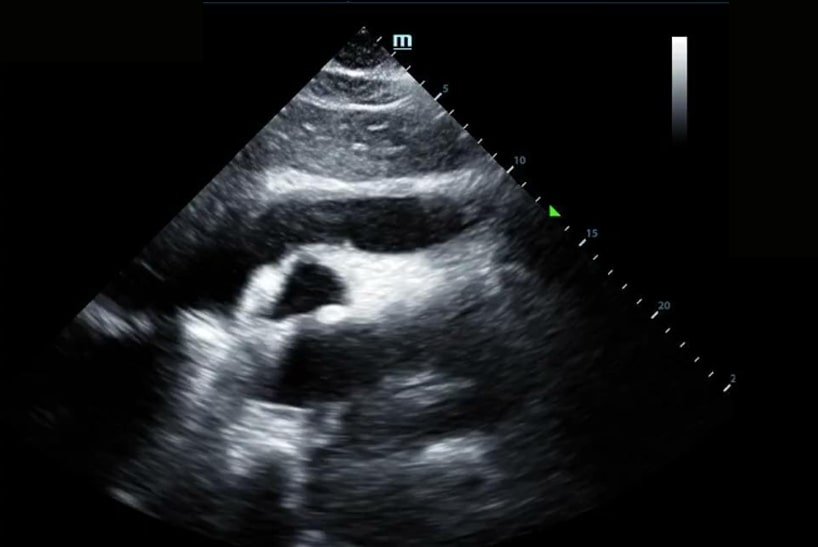

When asked to lie flat for the cardiac exam, he noted worsening chest discomfort. Upon obtaining the initial Parasternal Long Axis (PLAX) view, all eyes in the room grew wide in surprise.

Here you can see a significant pericardial effusion in PLAX and Subxiphoid views with concerns for early tamponade. This was communicated with the cardiology team who promptly drained 400cc of serosanguinous fluid. Ultimately there was no obvious source for this effusion. Since this experience, I always make sure to take at least a quick peek at the heart in respiratory cases where lung ultrasound is unrevealing.